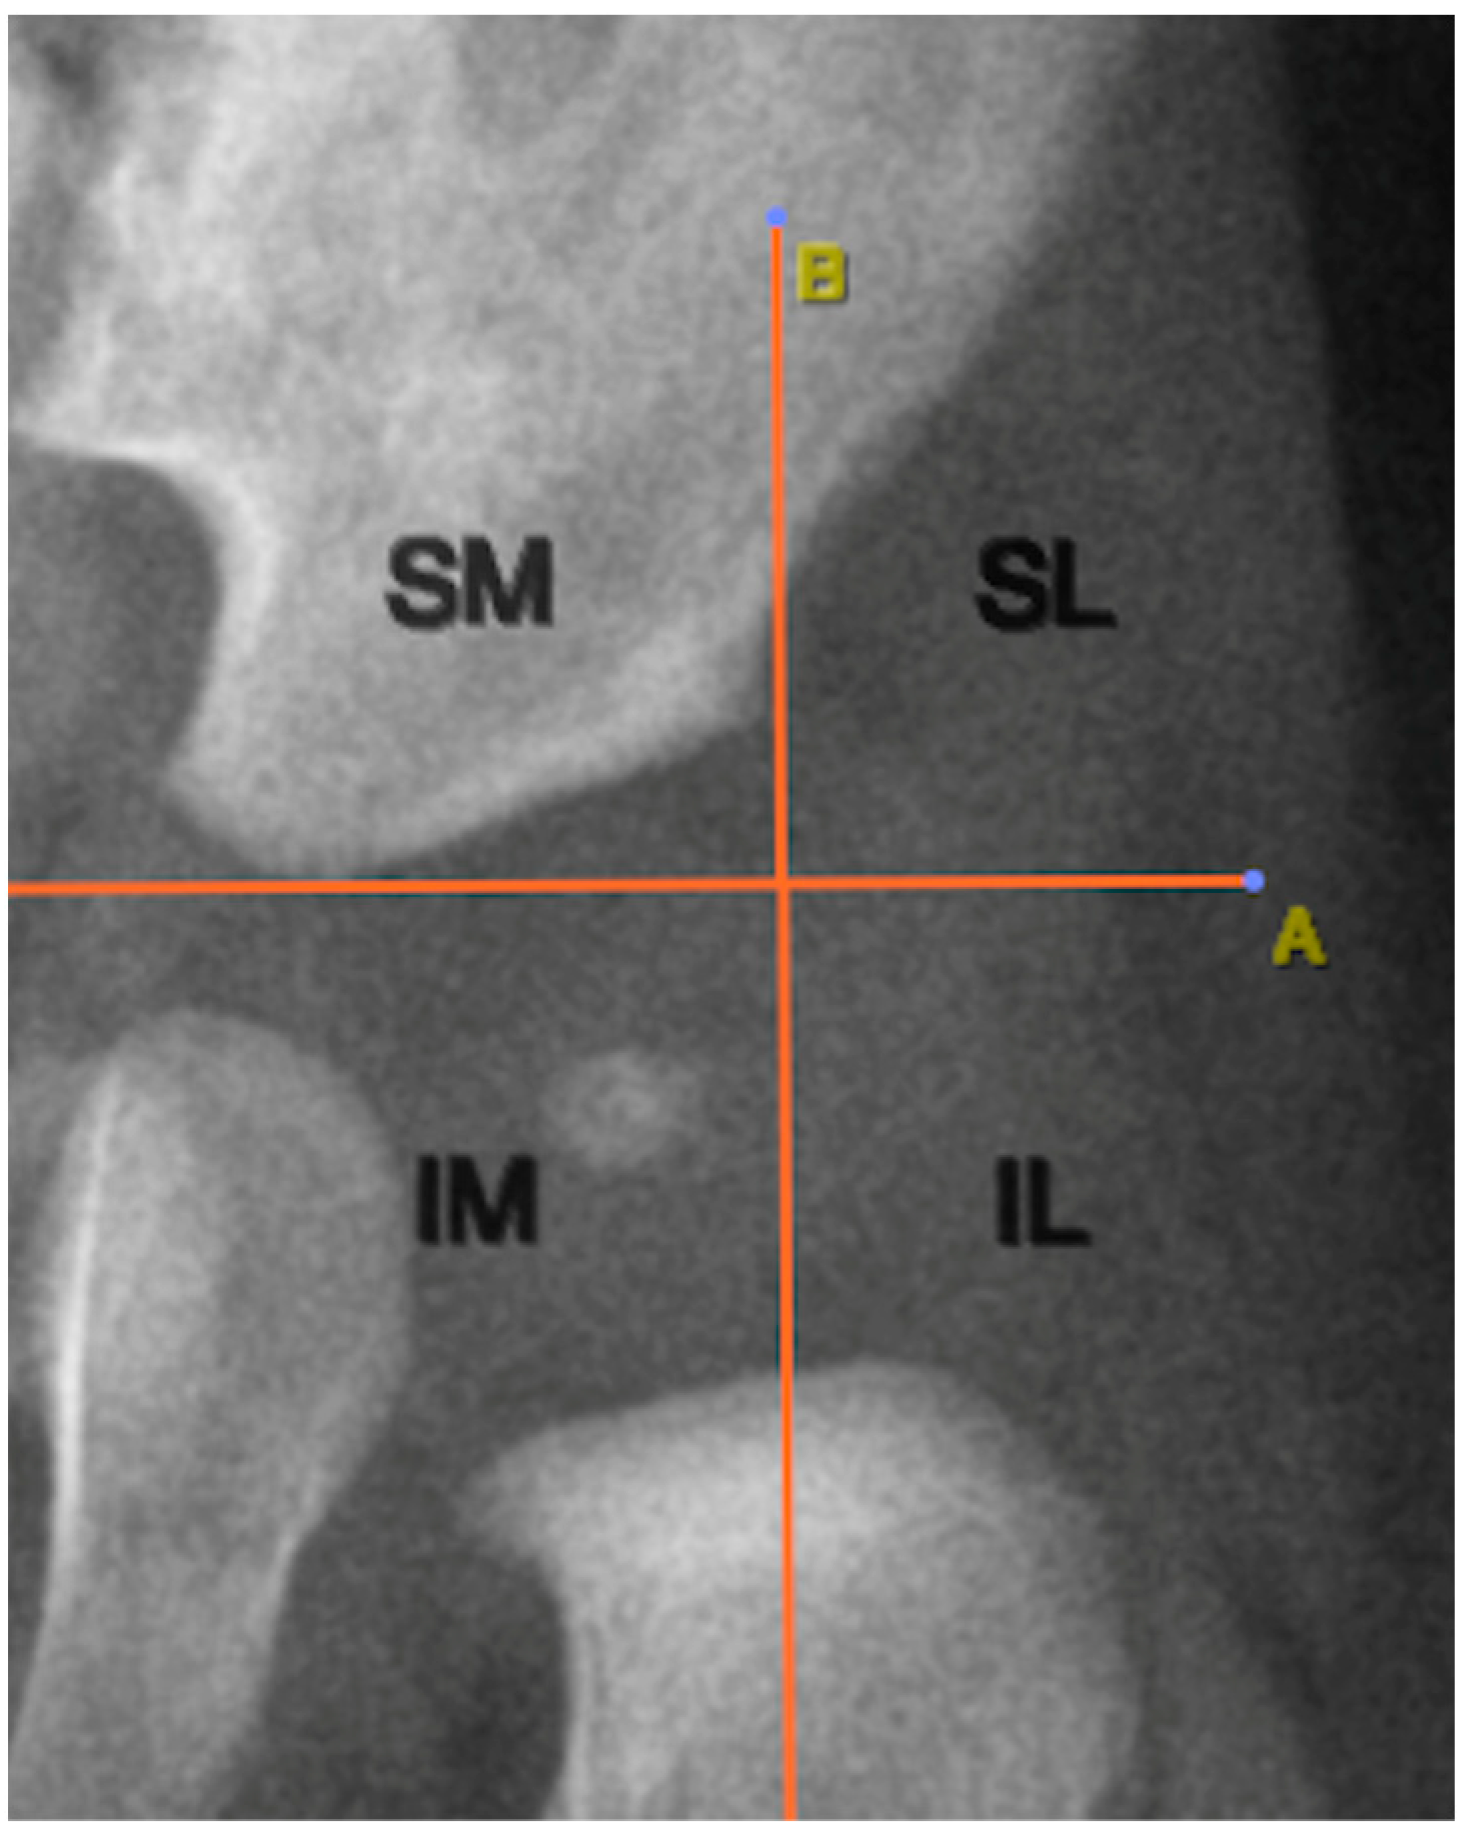

2.8. Positioning of the ONFH Relative to Anatomical Structures

The location of the ONFH was determined using two anatomical reference lines traced on the radiographic image. The first was Hilgenreiner’s line, a horizontal line connecting the lowest points of the triradiate cartilage of both iliac bones. Perkin’s lines extended perpendicular to Hilgenreiner’s line from the lateral acetabular edge. These lines created four quadrants: superolateral, superomedial, inferolateral, and inferomedial. Figure 4 illustrates this anatomical segmentation as applied to ONFH localization.

Analysis of ONFH localization revealed that all nuclei (100%) were located in the inferomedial quadrant, as defined by Hilgenreiner’s and Perkin’s lines (Figure 4).

Among the imaging analyses specific to pediatric pelvic radiography, the positioning of the ONFH is of particular interest. In our study, all cases of ONFH were located in the inferomedial quadrant of the hip joint, as defined by Hilgenreiner’s and Perkin’s lines, suggesting that this represents their normal physiological location. Therefore, the presence of the ONFH outside this quadrant could be indicative of hip dislocation [15].

Figure 4. Quadrant-based localization of the ONFH relative to adjacent structures. A: Hilgenreiner’s line; B: Perkin’s lines; SM: superomedial quadrant; SL: superolateral quadrant; IL: inferolateral quadrant; IM: inferomedial quadrant.